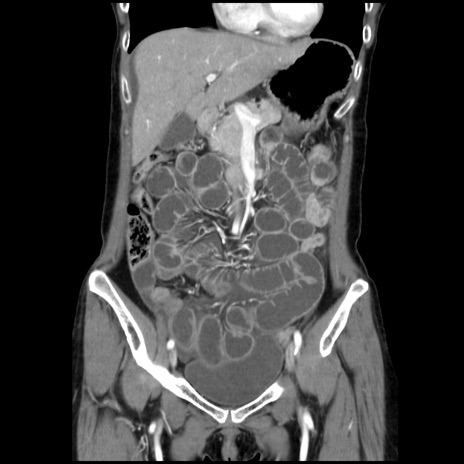

症例32(冠状断像)

【症例】40歳代 女性

【主訴】上腹部痛、嘔気・嘔吐

【現病歴】約9時間前頃から急に上腹部痛、嘔気、嘔吐が出現。改善しないため救急要請。

【既往歴】子宮頚癌(広汎子宮全摘術、放射線療法)、腸閉塞

【身体所見】腹部:平坦、軟、腸雑音亢進、上腹部を中心に腹部全体に圧痛あり。

【データ】WBC 8400、CRP 0.03